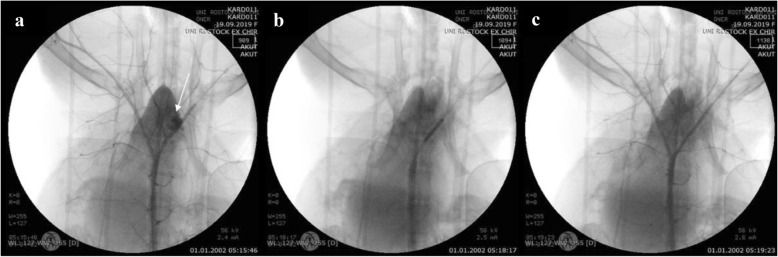

During the guidewire-induced vessel perforation, a cavity spilling of contrast media extravasation was clearly visible on angiography (Fig. 2a). After placing a covered stent graft (Fig. 2b) on the perforation site, the leakage was staunched (Fig. 2c).

Fig. 2.

Angiography of the iliac artery perforation via guidewire. a Cavity filling with blood after the vessel was injured with the Confianza PRO 12 guidewire. b Placing of a covered stent graft over the perforation site. c Verification of the leakage being sealed following stent implantation